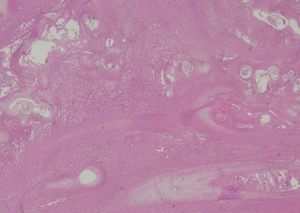

Complete excision of the horn was done with V-Y plasty, and the tissue was sent for pathological examination. A coiled horn measuring 26 cm with an attached skin ellipse measuring 4.5 x 3 cm was received in the pathology laboratory. Histopathological examination revealed a well-differentiated squamous cell carcinoma with keratin horn formation (Figs. 3 and 4). The tumour involves the upper dermis only with no vascular or perineural invasion. The lesion was completely excised with clear excision and deep margins measuring > 4mm. The patient’s surgical excision site healed well (Fig. 5), and there were no clinical recurrences over the 5-year period (the patient was seen at 3, 4, and 5 years after excision).